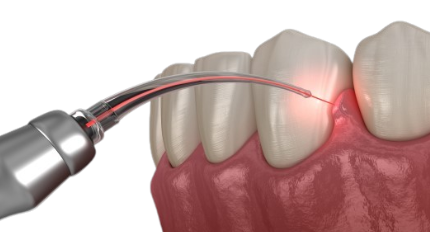

LASER stands for Light Amplification by the Stimulated Emission of Radiation. The instrument creates light energy in a very narrow and focused beam. This narrow focused beam produces a reaction when it hits the tissue, allowing it to remove or shape the tissue.

Nowadays, a variety of dental diseases are treated with lasers in dentistry. Compared to drills or other non-laser instruments, it has provided a more comfortable treatment option for some dental operations involving tissues.

Laser Dentistry is a cutting-edge method to dental care that has numerous advantages over traditional procedures. We are happy to provide this state-of-the-art equipment in our office to enhance your dental visit.

It uses focused light beams to treat dental issues. Lasers can vaporize or shape tissue precisely.